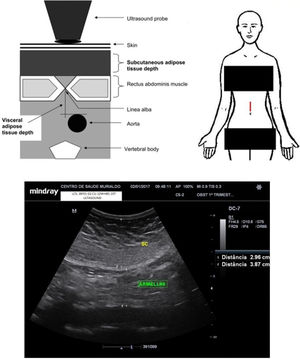

Maternal periumbilical fat evaluationMaternal periumbilical fat tissue was assessed with a convex probe placed 2cm above the maternal umbilical scar, aiming to measure the visceral and subcutaneous components using a method adapted from the studies by Armellini et al.18 An electronic calliper was placed spanning from the anterior aortic wall to the linea alba to assess the periumbilical maternal visceral adipose tissue (periumbilical m-VAT). Thereafter, the electronic calliper was moved to span from the linea alba to the superficial dermal edge, aiming estimate the periumbilical maternal subcutaneous adipose tissue (periumbilical m-SAT). The mean of the two measurements was calculated for both visceral fat assessments, the first at the end of maternal inspiration and the second at the end of maternal expiration. Fig. 2 shows the ultrasound measurements.